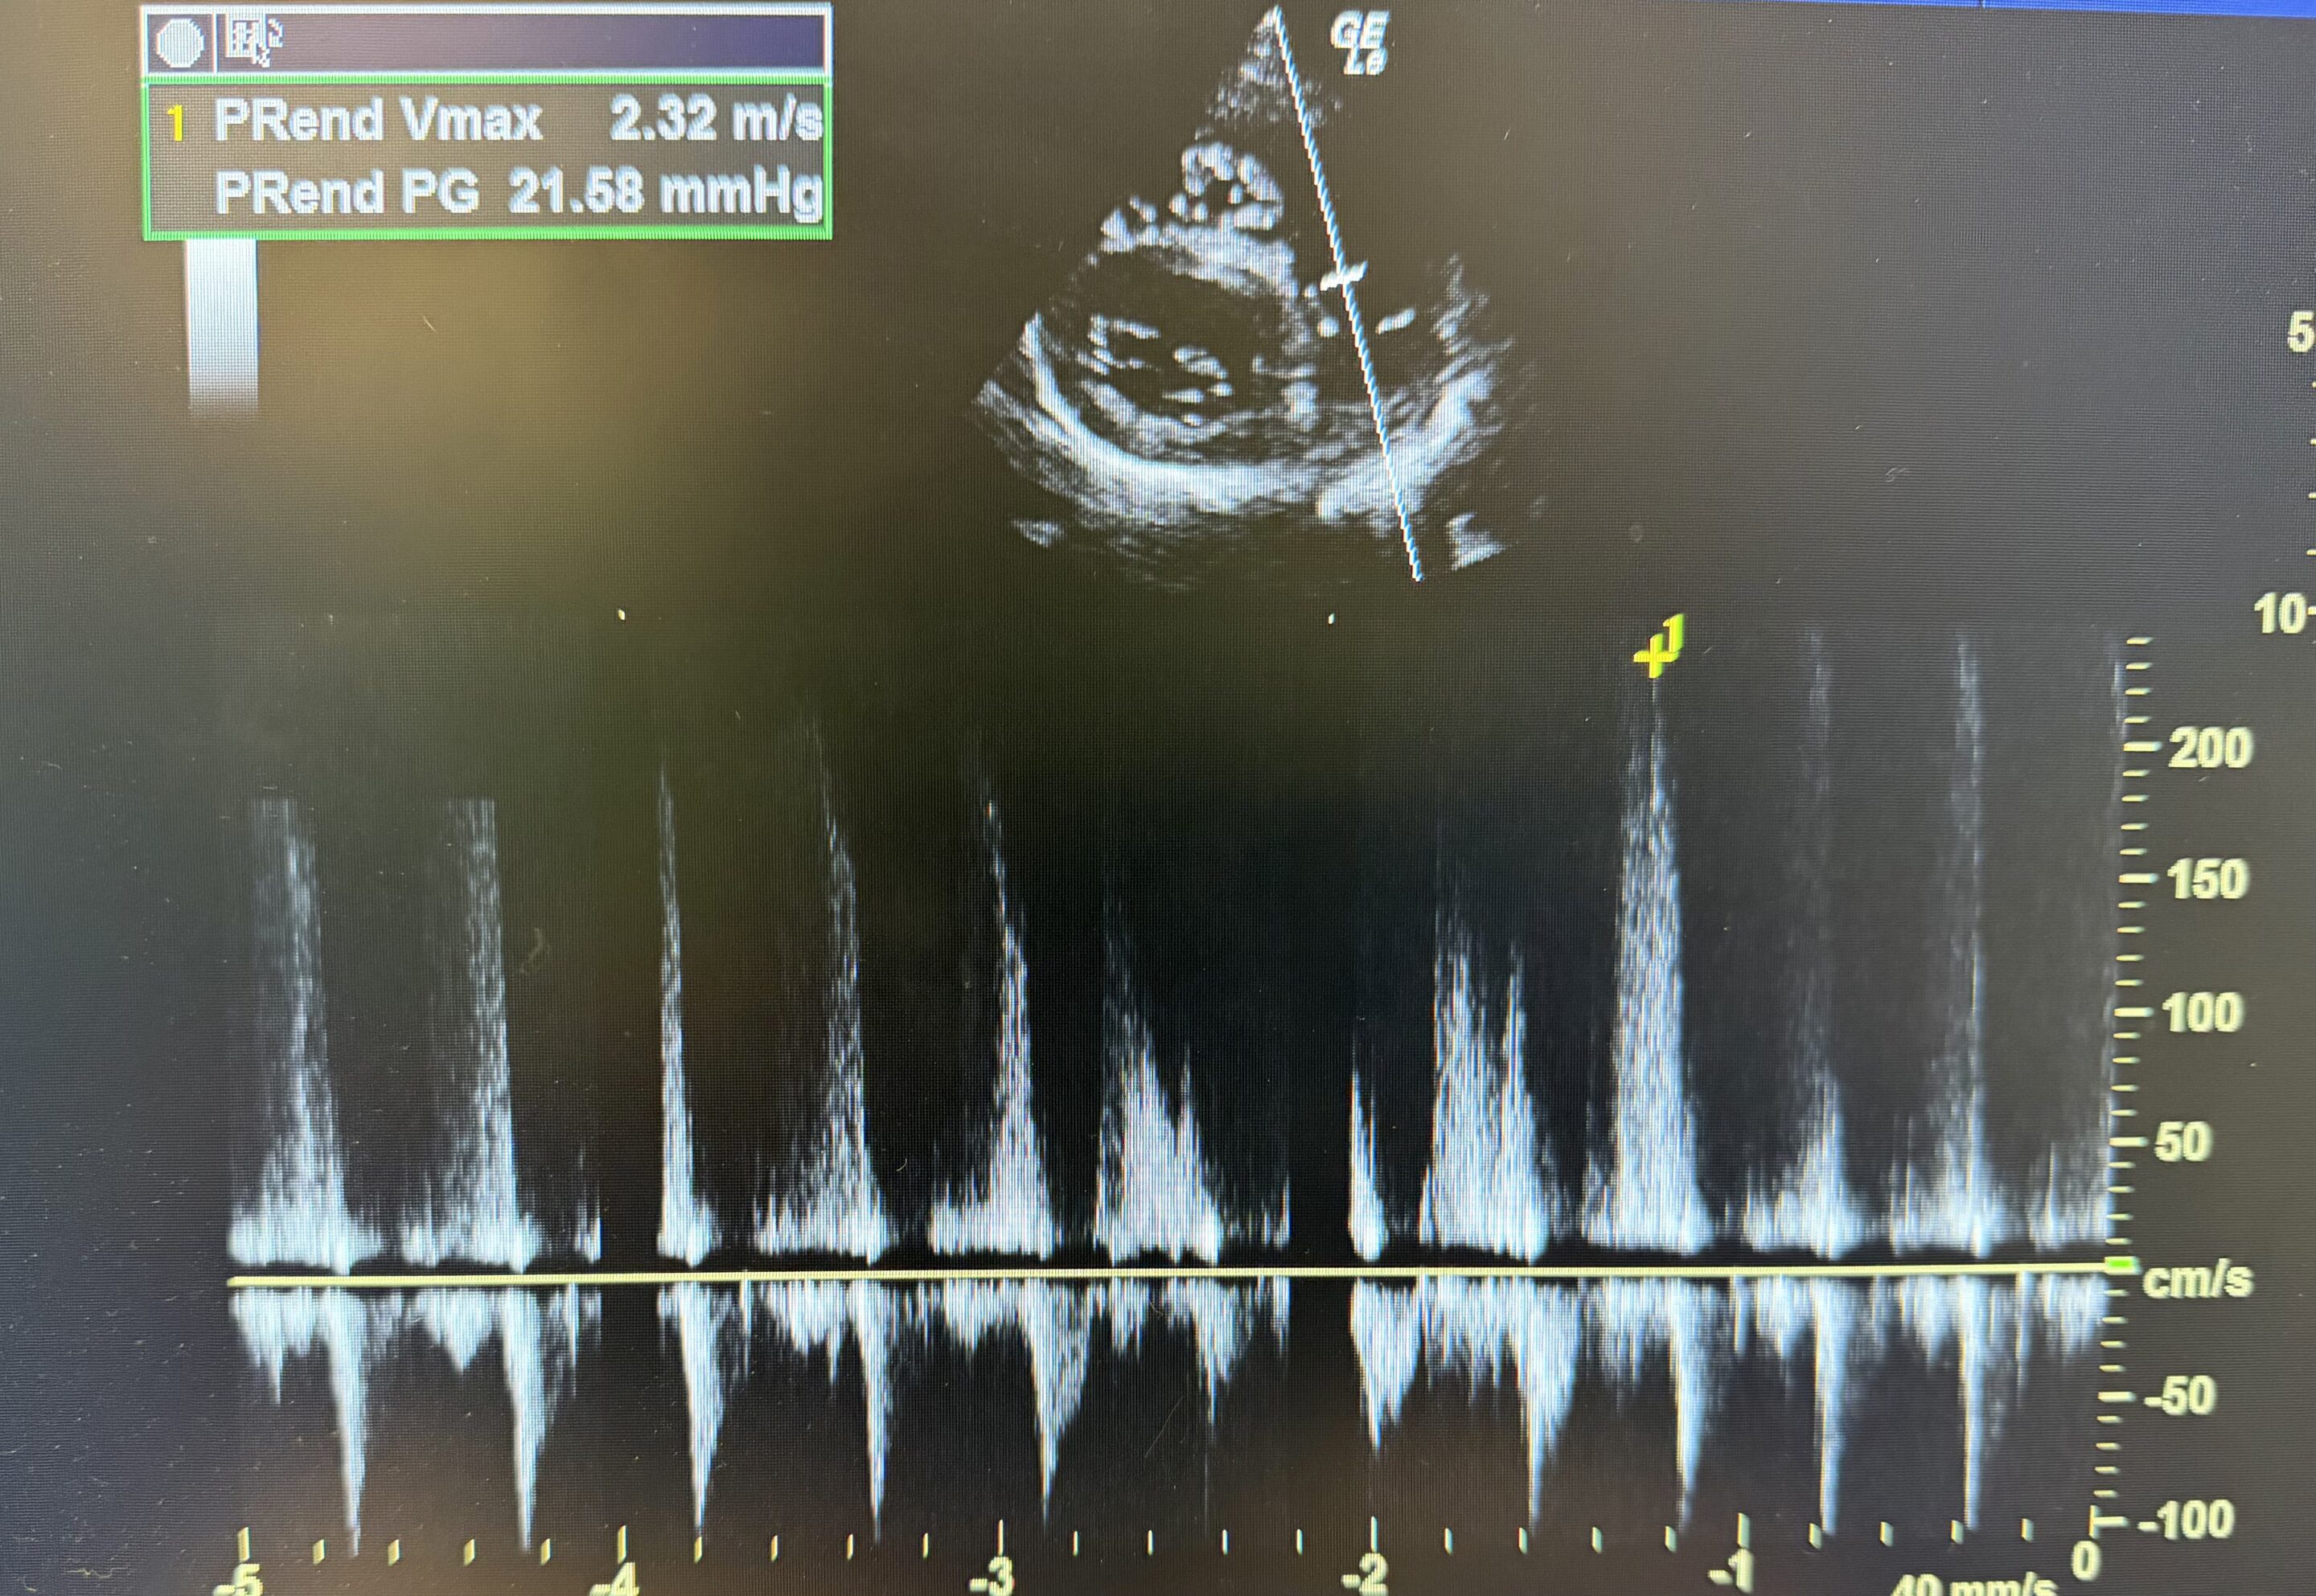

A pet ultrasound is a diagnostic imaging technique that uses sound waves to create real-time images of your pet’s internal organs. This painless procedure allows veterinarians to examine areas such as the heart, liver, kidneys, bladder, and abdominal organs without the need for surgery or invasive tests. It is often used to assess soft tissue structures and monitor ongoing conditions.

- Comprehensive Diagnostics: In addition to ultrasounds, Dr. Treadwell performs ultrasound guided aspirates, biopsy, and fluid removal. Dr. Treadwell uses ultrasound in addition to other specialty labs for complete assessment of your pet’s health.